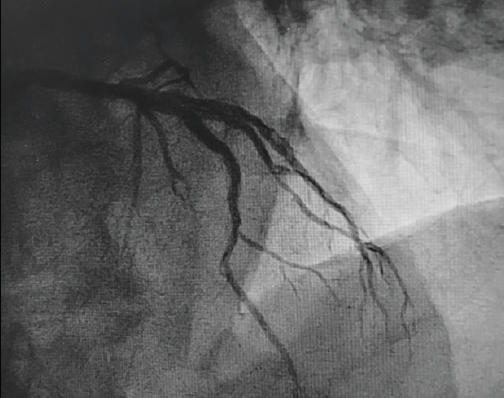

An 88-year-old man presented with cardiac symptoms including intrascapular discomfort that may be an anginal variant, dyspnea with exertion, obstructive sleep apnea, and easy fatigability. His body mass index was 36 kg/m2. He also reported episodes of shortness of breath. The patient’s thallium stress test and echocardiographic findings were normal. He was previously seen by an orthopedic surgeon for leg pain. Duplex examination showed bilateral common femoral artery velocity reduction of 0.65 cm on the right and 0.64 cm on the left; the superficial femoral artery reduction was 0.39 cm on the right and 0.51 cm on the left; and the popliteal artery reduction was 0.33 cm on the right and 0.46 cm on the left side. Diagnostic angiographic findings demonstrated severe proximal, mid, and distal LAD arterial disease (Figure 1), as well as obtuse marginal disease. The patient was a poor candidate for surgical revascularization.

A right radial approach using a 7-F Glidesheath™ Slender device (Terumo Interventional Systems) was selected, and heparin was administered throughout the procedure. A 7-F XB LAD guide catheter was engaged after poor mapping of the first guide, followed by a 0.014-cm BMW guidewire. Balloon angioplasty of the proximal LAD was performed with a 2.5-mm balloon. A 4- X 24-mm EluNIR™ stent was deployed in the proximal LAD. The second stent, a 3.5- X 20-mm EluNIR™, was placed in the mid-LAD with the assistance of a GuideLiner® device (Teleflex). The very distal LAD artery lesion requires predilatation with a 2-mm balloon before deployment of the third stent, a 2.5- X 24-mm EluNIR™. A 3.5-mm noncompliant balloon was used to “touch up” the middle of the stents. The procedure concluded with no complications (Figure 2).

Before the procedure, the patient had 90% to 95% proximal LAD stenosis and 0% stenosis postintervention. Findings also included extreme mid-LAD calcification (50%–70%) preprocedure and 0% calcification postintervention. The distal LAD stenosis was 95% before the procedure and 0% after stenting. However, there was approximately 60% to 70% distal LAD artery disease just above the wraparound portion, which was not treated. Fortunately, the diagonal branch that was located at the proximal lesion of the LAD was not placed in a stent jail.